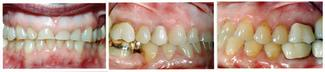

The patient was pleased with the results (Figure 3). The crowns restored adequate function and esthetics, and the vertical dimension was achieved through orthodontic movement. Interdisciplinary treatment enabled the patient to regain good esthetics and improve her self-esteem.

The patient presented with a history of bulimia, which resulted in severe erosion, incisal wear, and over-eruption of the mandibular teeth. She reported her bulimia was under control, and she wanted to improve her appearance and function. Interdisciplinary dental treatment was critical for a successful outcome. Dentists play an important role in the diagnosis of bulimia and in overall treatment. ■